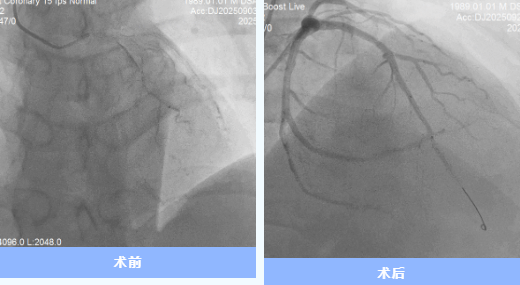

患者到院后,團(tuán)隊(duì)立即實(shí)施急診PCI手術(shù)。術(shù)中造影顯示前降支近端完全閉塞,雖經(jīng)球囊擴(kuò)張、血栓抽吸等操作,仍出現(xiàn)“無復(fù)流”現(xiàn)象。IVUS檢查提示冠脈內(nèi)彌漫性血栓,團(tuán)隊(duì)討論后決定暫不植入支架,先開展強(qiáng)化抗栓抗板治療,待后續(xù)復(fù)查造影。

9月24日,經(jīng)過充分的術(shù)前評(píng)估,心內(nèi)科一病區(qū)介入團(tuán)隊(duì)為代先生復(fù)查冠脈造影并于前降支成功植入支架1枚。